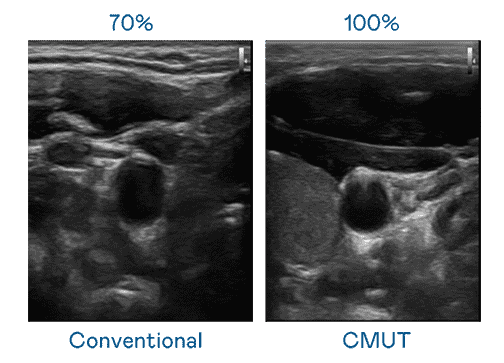

CMUT 技术是一种用电容式微机电元件来产生超音波讯号的技术。。。。与传统 PZT 压电式技术相比,,,,CMUT 频宽增加 30%,,,,更宽频的超音波讯号让影像解析度大幅提升,,,是实现高影像品质医疗超音波扫描、、、、促进精准医疗发展的关键技术。。。

大频宽带来超清晰影像

超音波影像的解析度高低,,首先取决于探头能发出的讯号频宽。。。至成国际 CMUT 可提供高清晰的超音波讯号,,提供高频宽、、高灵敏度、、影像纹理细节更高的超音波影像,,,,协助医护人员缩短影像判读时间及利用精准的医疗影像进行诊断。。。